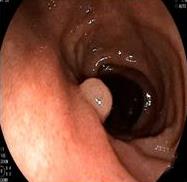

• 内镜诊断和治疗十二指肠黏膜下恒径动脉破裂出血并活动性出血的价值(附6例报告)

2026, 32(1):80-83. DOI: 10.12235/E20250357

摘要 (39) HTML (37) PDF 1.21 M (63) 评论 (0) 收藏

摘要:目的 探讨内镜诊断和治疗十二指肠黏膜下恒径动脉破裂出血并活动性出血的价值。方法 回顾性分析2015年6月-2023年1月该院经内镜确诊十二指肠黏膜下恒径动脉破裂出血并活动性出血的6例患者的临床资料。总结临床表现、内镜下特征和治疗转归。结果 于24 h内完成急诊内镜检查,证实6例均为单纯十二指肠黏膜下恒径动脉破裂出血,并成功行内镜下钛夹止血治疗。结论 内镜诊断十二指肠黏膜下恒径动脉破裂出血所致的大出血,具有较高的价值。此外,于内镜下及时采取积极、有效的干预措施,可快速止血,降低死亡率。值得应用于临床。